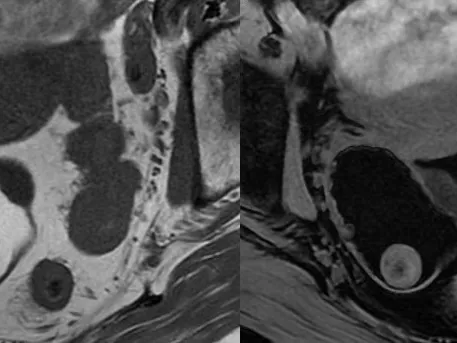

▶ Part 2 covers: MRI Adnexal Lesion Characterisation / Ovarian Cancer Staging / Chronic Pelvic Pain / Endometriosis / Acute Pelvic Pain / Imaging of Mesh Complications / Vulval Cancers

- Lectures on reading female pelvic MRI for diagnosis of uterine anomalies, adnexal lesion characterisation, evaluation of acute and chronic pelvic pain, evaluation of uterine fibroids and staging and follow up of uterine malignancies